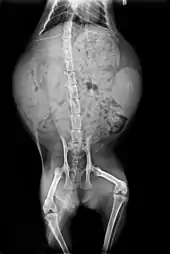

Radiography of a pregnant cat. The skeletons of two fetuses are visible on the left and right of the uterus.

After mating, the female cleans her vulva thoroughly. If a male attempts to mate with her at this point, the female attacks him. After about 20 to 30 minutes, once the female is finished grooming, the cycle will repeat.[149] Because ovulation is not always triggered by a single mating, females may not be impregnated by the first male with which they mate.[150] Furthermore, cats are superfecund; that is, a female may mate with more than one male when she is in heat, with the result that different kittens in a litter may have different fathers.[149]